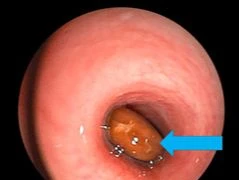

Nội soi gắp dị vật trong phế quản gốc của bệnh nhân

Ho khó thở, cụ ông 81 tuổi phát hiện răng mắc ở phế quản gốc

Khi phát hiện bệnh nhân có những dấu hiệu nguy hiểm sau ăn như khó thở, ho nhiều, cần cho bệnh nhân ngồi hoặc nằm nghiêng vỗ mạnh dứt khoát vào lưng...